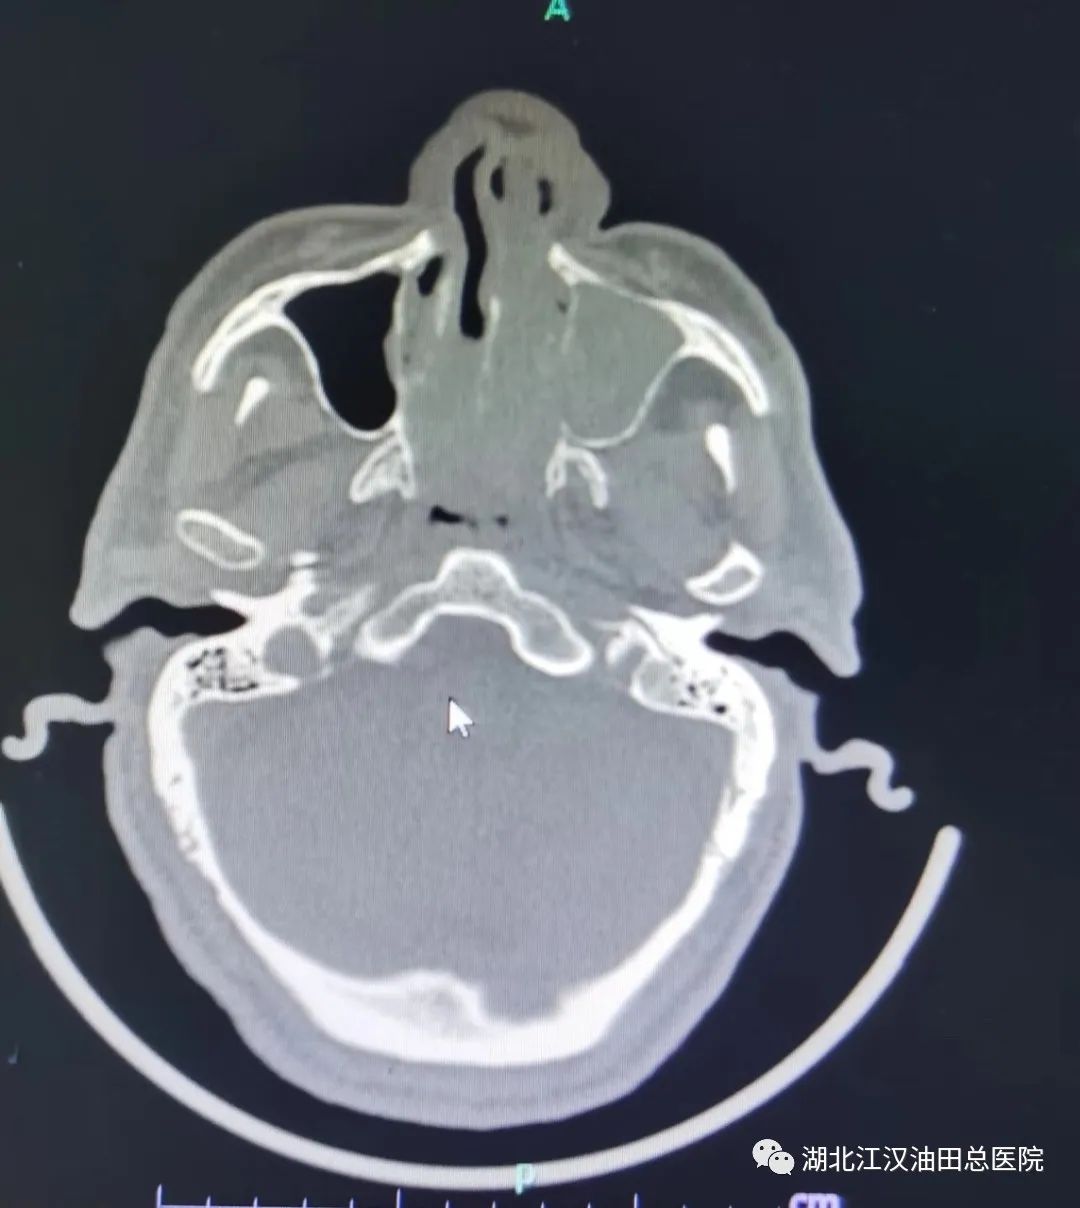

患者姜老中医被鼻塞的问题困扰了3年多,病情不断加重。呼吸受到明显阻碍,打鼾憋气,偶尔头痛头昏,口感不适,嗅觉也明显减退。由于一直没有查找出原因,姜老中医心情十分焦虑。今年11月初,他在家人的陪同下,来到油田总医院耳鼻喉科就诊。接诊医生诊断他的左侧鼻腔被长出的息肉堵住了,后鼻孔也被堵住了。

经周密的术前准备,11月3日,叶成刚医生主刀为这名老中医患者实施了手术治疗。手术麻醉科主任赵铤为其制定了个性化麻醉方案,在麻醉科医护人员配合下,实施了全麻鼻内镜下内肿物切除术+鼻窦开放术+窦内病变清除术+下甲成形术。手术过程非常顺利,麻醉也达到了理想的效果。术后予以吸氧、止血、预防感染及对症治疗。术后的病检显示,姜老中医患的是左侧鼻腔及上颌窦慢性鼻窦炎,鼻咽部粘膜慢性炎症,与术前诊断非常吻合。